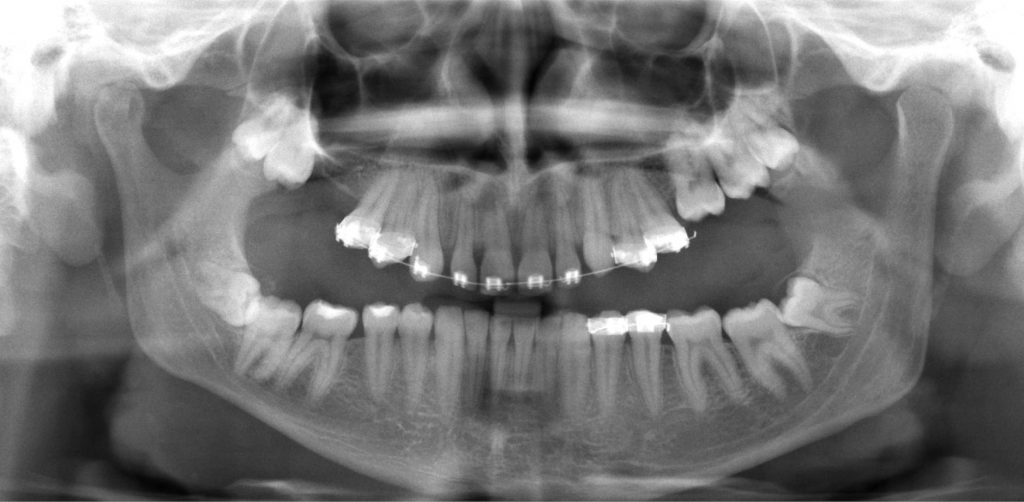

Streszczenie: Zaburzenia wyrzynania zębów ze względu na różnorodną etiologię, obraz kliniczny i radiologiczny dzielimy na: pierwotne zaburzenie wyrzynania (PFE), wtórne zaburzenie wyrzynania (MFE), ektopowe zaburzenie wyrzynania (EEM) i zatrzymanie/zaklinowanie zęba. Kluczowe z punktu widzenia powodzenia leczenia jest prawidłowe zróżnicowanie zaburzenia, dlatego też powinniśmy kłaść nacisk przede wszystkim na dokładną diagnostykę. Pozwoli to na wybór optymalnego planu leczenia i uchroni przed zbędnymi powikłaniami.